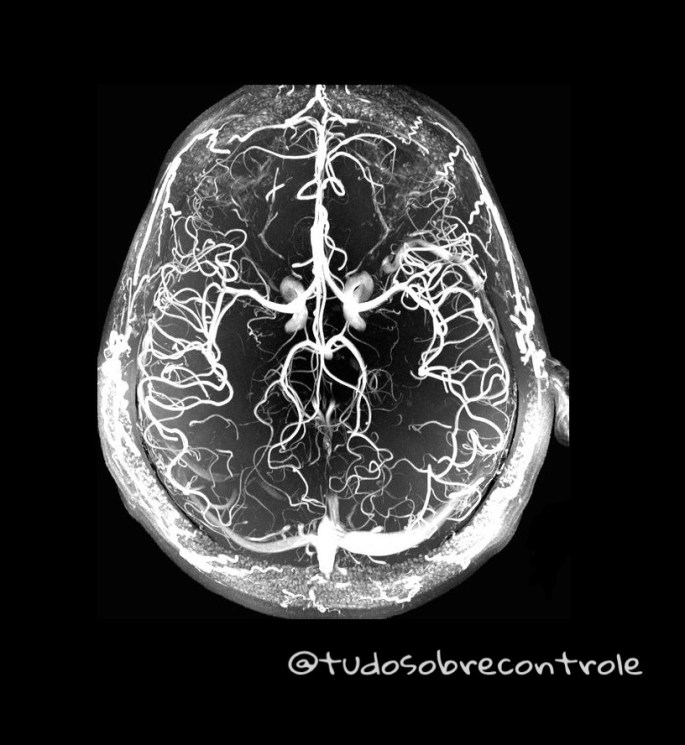

Em Novembro, um grupo de neurocientistas de uma universidade americana mostrou que a infecção pelo vírus Zika também causa microcefalia. Após o nascimento, o Zika restringe o crescimento do encéfalo por alterar os vasos sanguíneos cerebrais e a barreira hematoencefálica e aumentar a inflamação cerebral levando a morte maciça de neurônios e microcefalia no cérebro em desenvolvimento. Isso acontece porque o cérebro humano está em desenvolvimento até os 3 anos de idade. Então se você é mãe ou pai proteja seu filho dos mosquitos tomando os cuidados necessários descritos aqui.